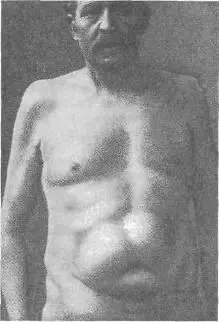

Рис. 37. Двусторонняя грыжа спигелиевой линии (Wullstein).